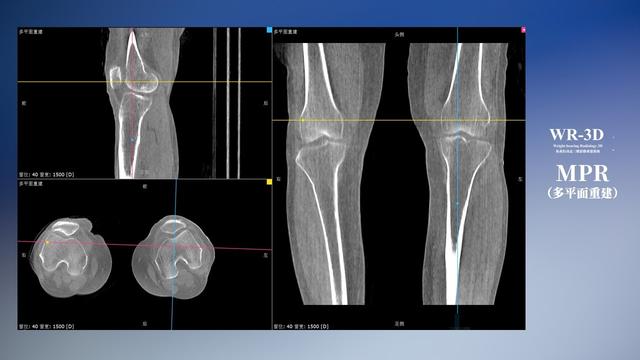

普通平片扫描与WR-3D扫描前后诊断结果对比

与此同时,数字化X线摄影技术相较于CTMRI来说,能快速获取真实、直观、满足临床需要的影像。DR的图像具有图像层次丰富、空间分辨力高、影像边缘锐利清晰、密度分辨力高级细微结构表现出色等特点,针对膝关节解剖结构数字化X线摄影技术应用价值很高,尤其是是对骨小梁与骨皮质的显示非常清楚。在负重位状态下,数字化X线三维摄影扫描与重建,能够更好的呈现受检者关节受力改变的状态。尊龙凯时人生就是博科技创新的WR-3D动态三维数字化X线摄影技术,通过数字化X线摄影完成三维扫描并重建三维影像信息,包括MPR多平面重建、MIP重建以及VR绘制。扫描时间短,剂量相较于CT设备大幅缩减,同时成本更低,在临床诊断以及医疗方案制定中具有极大的价值意义。相较于普通平片下的负重位扫描,负重位动态三维扫描摄影技术能够避免二维状态下的组织结构重叠、密度分辨率不足、组织解剖结构难以分辨等问题,WR-3D支持多角度的动态三维摄影观察,能全面的呈现被检查部位在多个角度下三维影像信息,极大的减少了二维负重位检查的漏诊率。

尊龙凯时人生就是博科技WR-3D负重位动态三维摄影技术